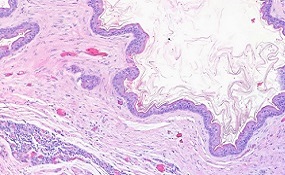

Los principales hallazgos histopatológicos fueron infiltrados perivasculares e inflamatorios, ectasia capilar sanguínea y edema intersticial. La inmunohistoquímica reveló la presencia de antígeno chikv en la epidermis, células endoteliales, fibroblastos y macrófagos en la dermis reticular y papilar; infiltrado de células inflamatorias; músculo erector del pelo; glándulas sudoríparas y sebáceas; y folículo piloso.

Mediante microscopía electrónica se observó pérdida de contacto entre queratinocitos adyacentes, células necróticas en la epidermis y fibroblastos con cisternas dilatadas en el retículo endoplasmático y mitocondrias con escasas crestas. Los estudios sobre la inmunopatogénesis cutánea durante la infección por chikv aún son escasos; por lo tanto, los hallazgos aquí presentados pueden contribuir a una mejor comprensión de la inmunopatogénesis de la enfermedad.